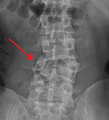

A burst fracture of L4 as seen on plane X ray